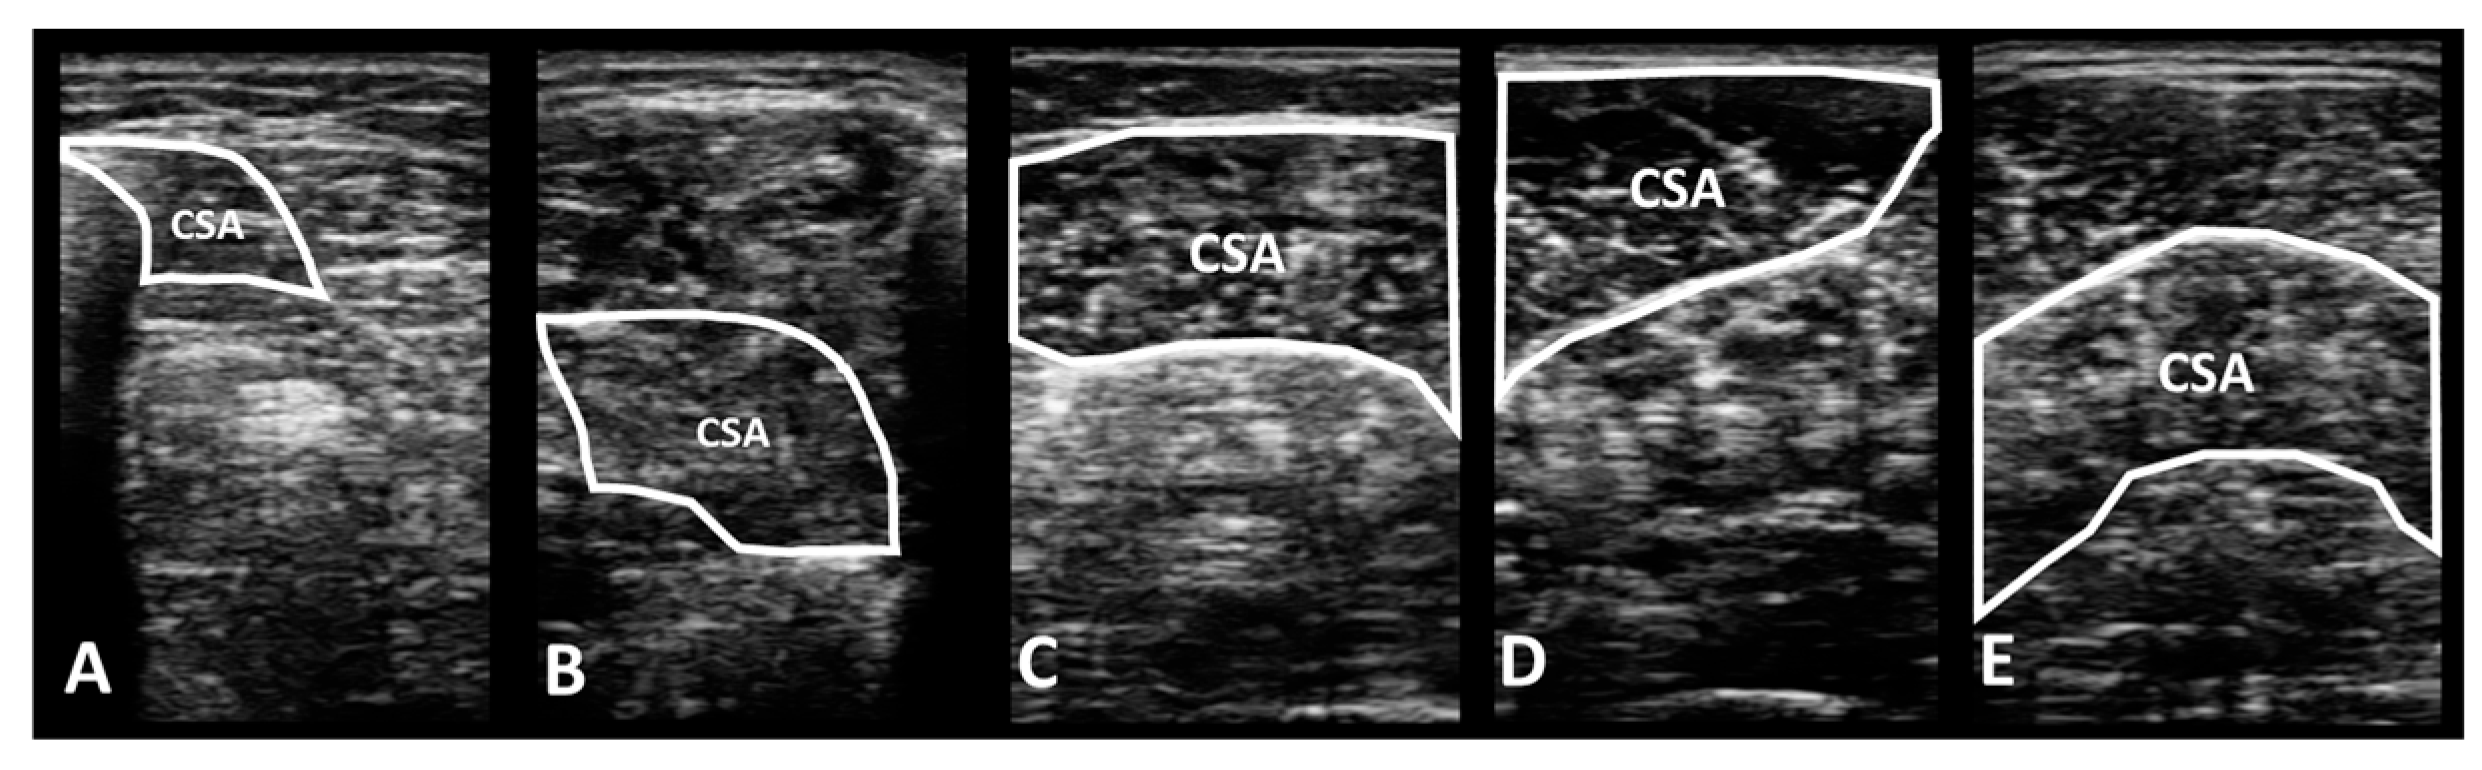

2.4.1. Portable Wireless Diagnostic Ultrasound Device

2.6. Data Processing